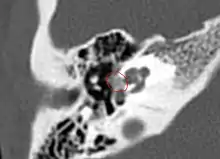

CT imaging

Imaging is usually not pursued in those with uncomplicated conductive hearing loss and characteristic clinical findings. Those with only conductive hearing loss are often treated medically or with surgery without imaging. The diagnosis may be unclear clinically in cases of sensorineural or mixed hearing loss and may become apparent only on imaging. Therefore, imaging is often performed when the hearing loss is sensorineural or mixed.

A high-resolution CT shows very subtle bone findings. However, CT is usually not needed prior to surgery.

Otosclerosis on CT can be graded using the grading system suggested by Symons and Fanning.[21]

- Grade 1, solely fenestral;

- Grade 2, patchy localized cochlear disease (with or without fenestral involvement) to either the basal cochlear turn (grade 2A), or the middle/apical turns (grade 2B), or both the basal turn and the middle/apical turns (grade 2C); and

- Grade 3, diffuse confluent cochlear involvement (with or without fenestral involvement).

CT scan of otosclerotic focus in the anterior footplate